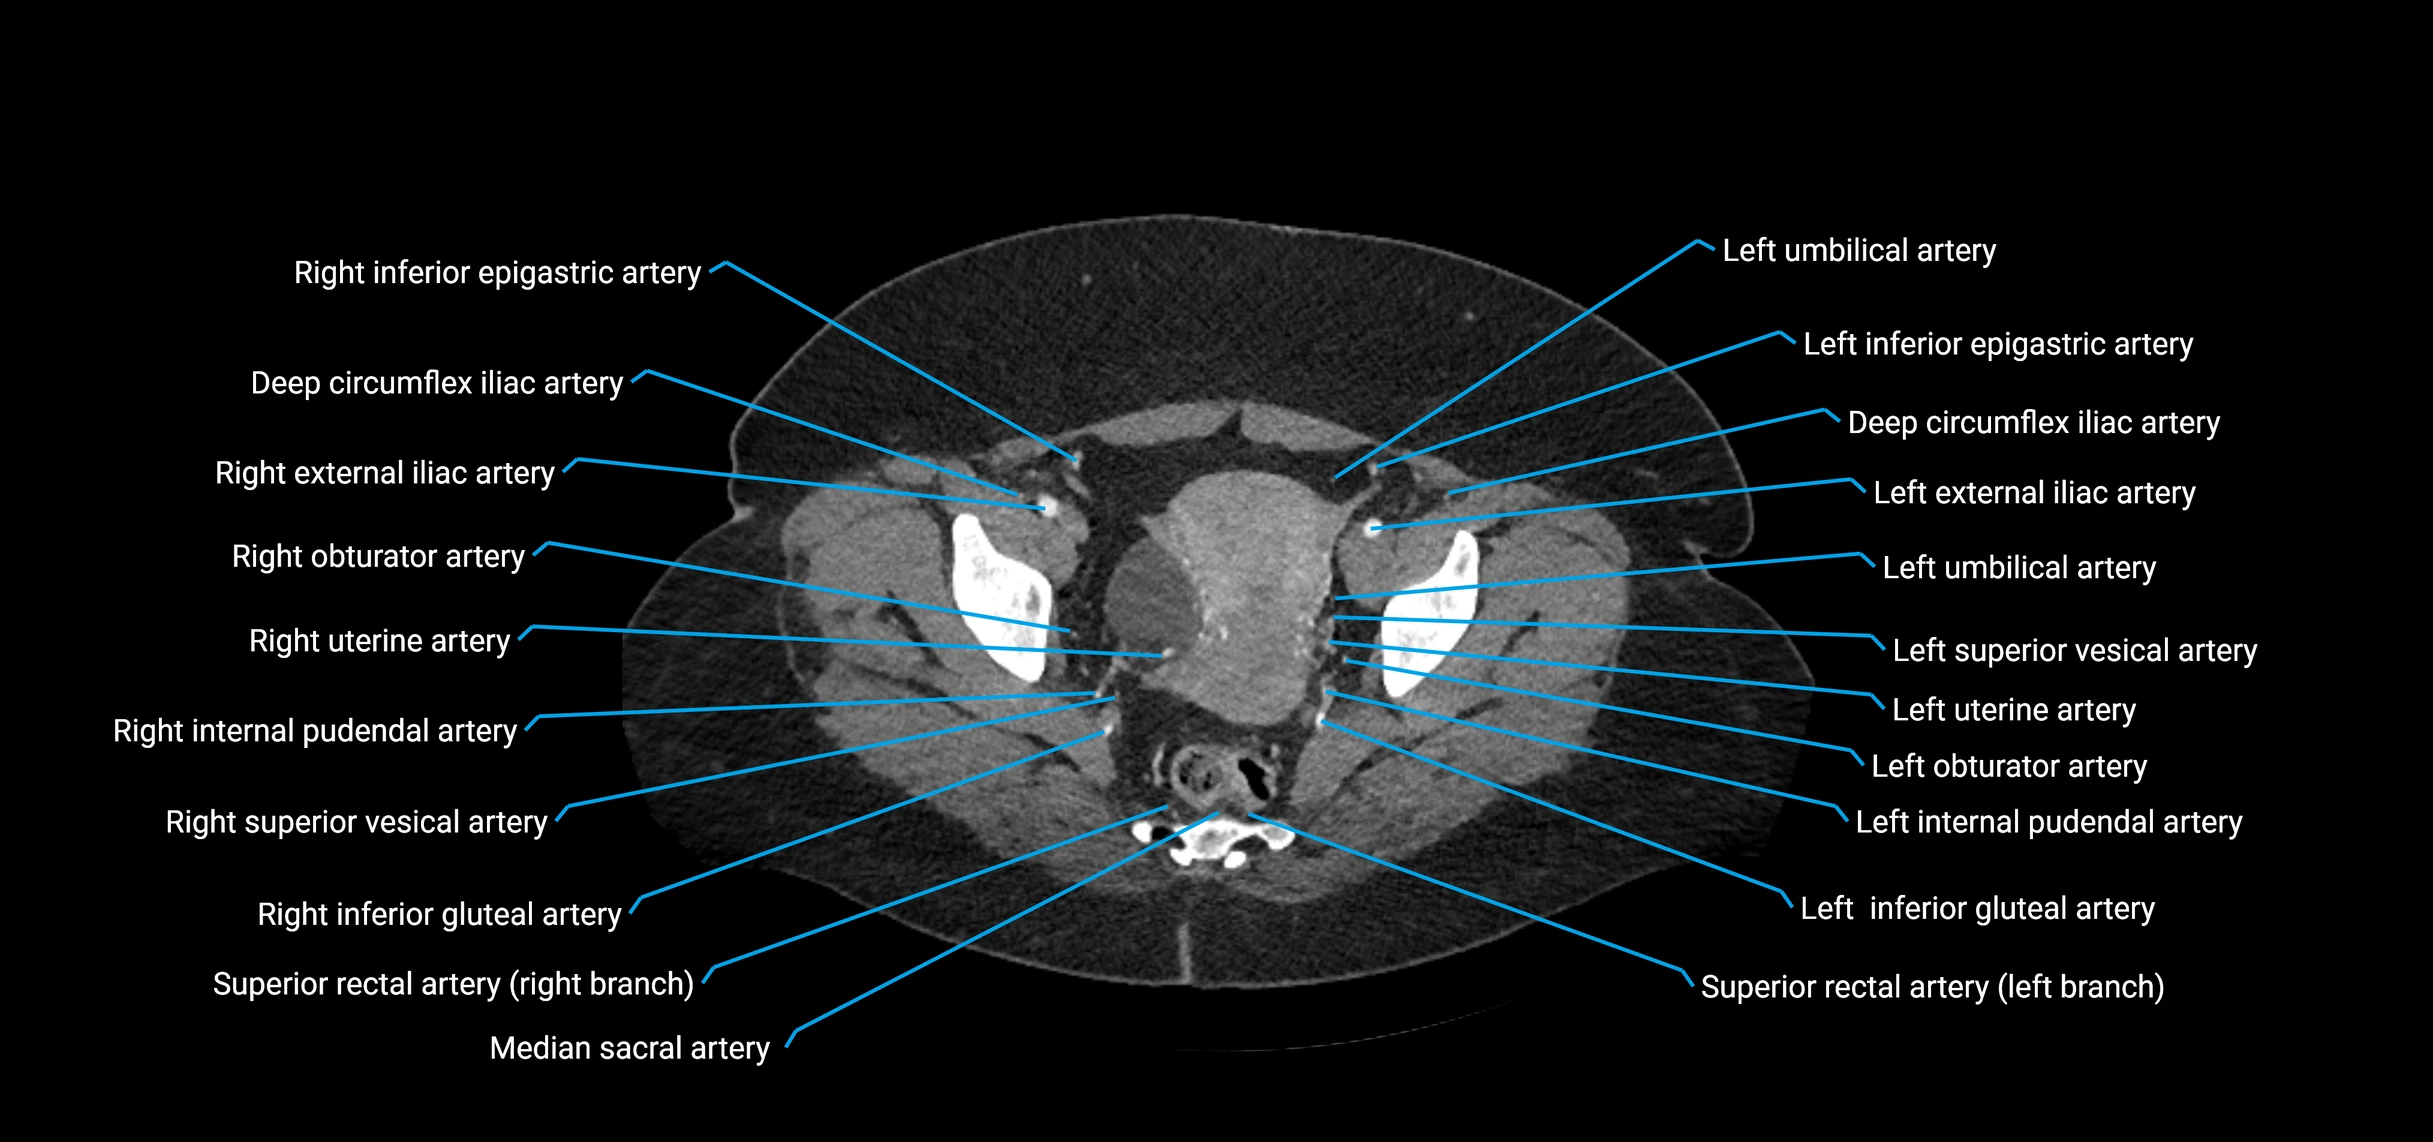

Contrast-enhanced CT (CTA):

• Gold standard for abdominal aortic imaging

• Provides excellent detail of lumen, wall, aneurysm, thrombus, and branch vessels

• Multiplanar and 3D reconstructions help in aneurysm measurement, stent graft planning, and dissection evaluation